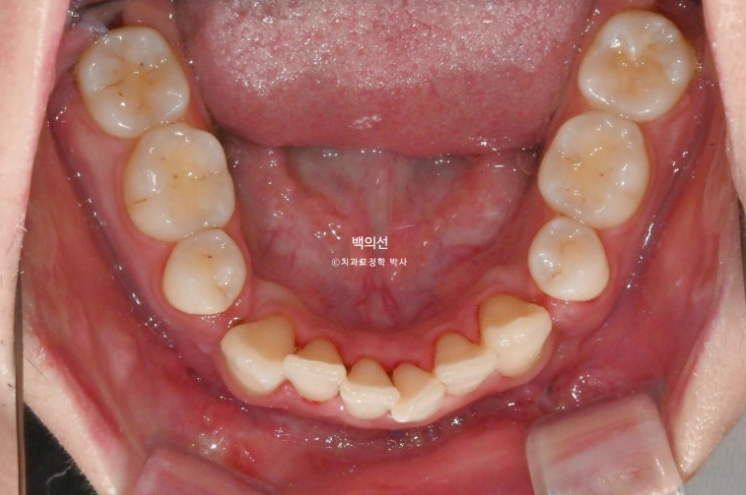

24년 10월, 돌출입 수술 한달 후 내원한 환자분 입니다.

24.10

돌출입 수술을 하면 수술 테크닉적으로 작은어금니가 있던 공간이 약 2mm 이상이 남게 됩니다.

송곳니 뒤쪽에 2mm 의 공간이 각각 남았습니다.

이렇게 애매하게 남은 공간을 앞니 배열을 위한 공간으로 사용하는 것이 돌출입 수술교정의 핵심입니다.

이 정도의 남은 공간은 14개의 장치 안에서 해결 가능하기에 인비절라인 라이트로 충분합니다.